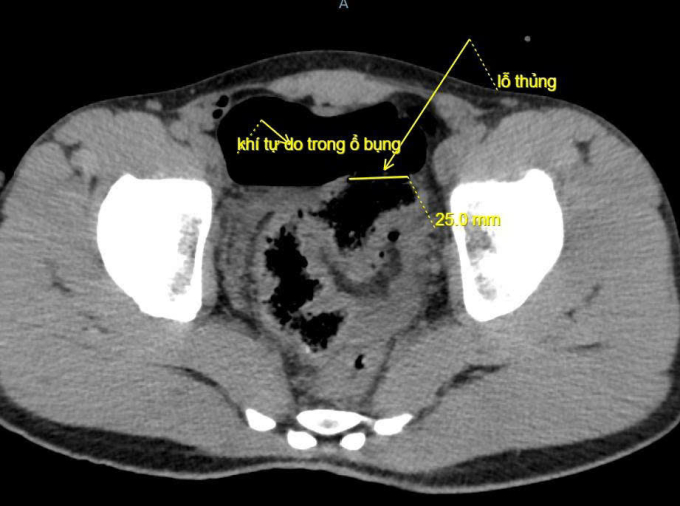

Ngày 20/10, đại diện Bệnh viện Đa khoa Lạng Sơn cho biết bệnh nhân đau bụng dữ dội, bụng chướng căng, khó thở và mệt lả. Kết quả chụp X-quang và CT thấy nhiều khí tự do trong ổ bụng bệnh nhân, bác sĩ nghi ngờ thủng tạng rỗng, chỉ định mổ cấp cứu.

Quá trình mổ, các bác sĩ ghi nhận khoảng 100 ml máu và dịch bẩn trong bụng bệnh nhân, đại tràng sigma có đoạn tổn thương dài 5 cm, thủng khoảng 2 cm và xung quanh dập nát. Bệnh nhân được cắt lọc lỗ thủng, khâu đoạn đại tràng tổn thương, làm sạch ổ bụng và đặt dẫn lưu.

Ảnh chụp CT ghi nhận đại tràng của bệnh nhân bị thủng. Ảnh: Bệnh viện cung cấp